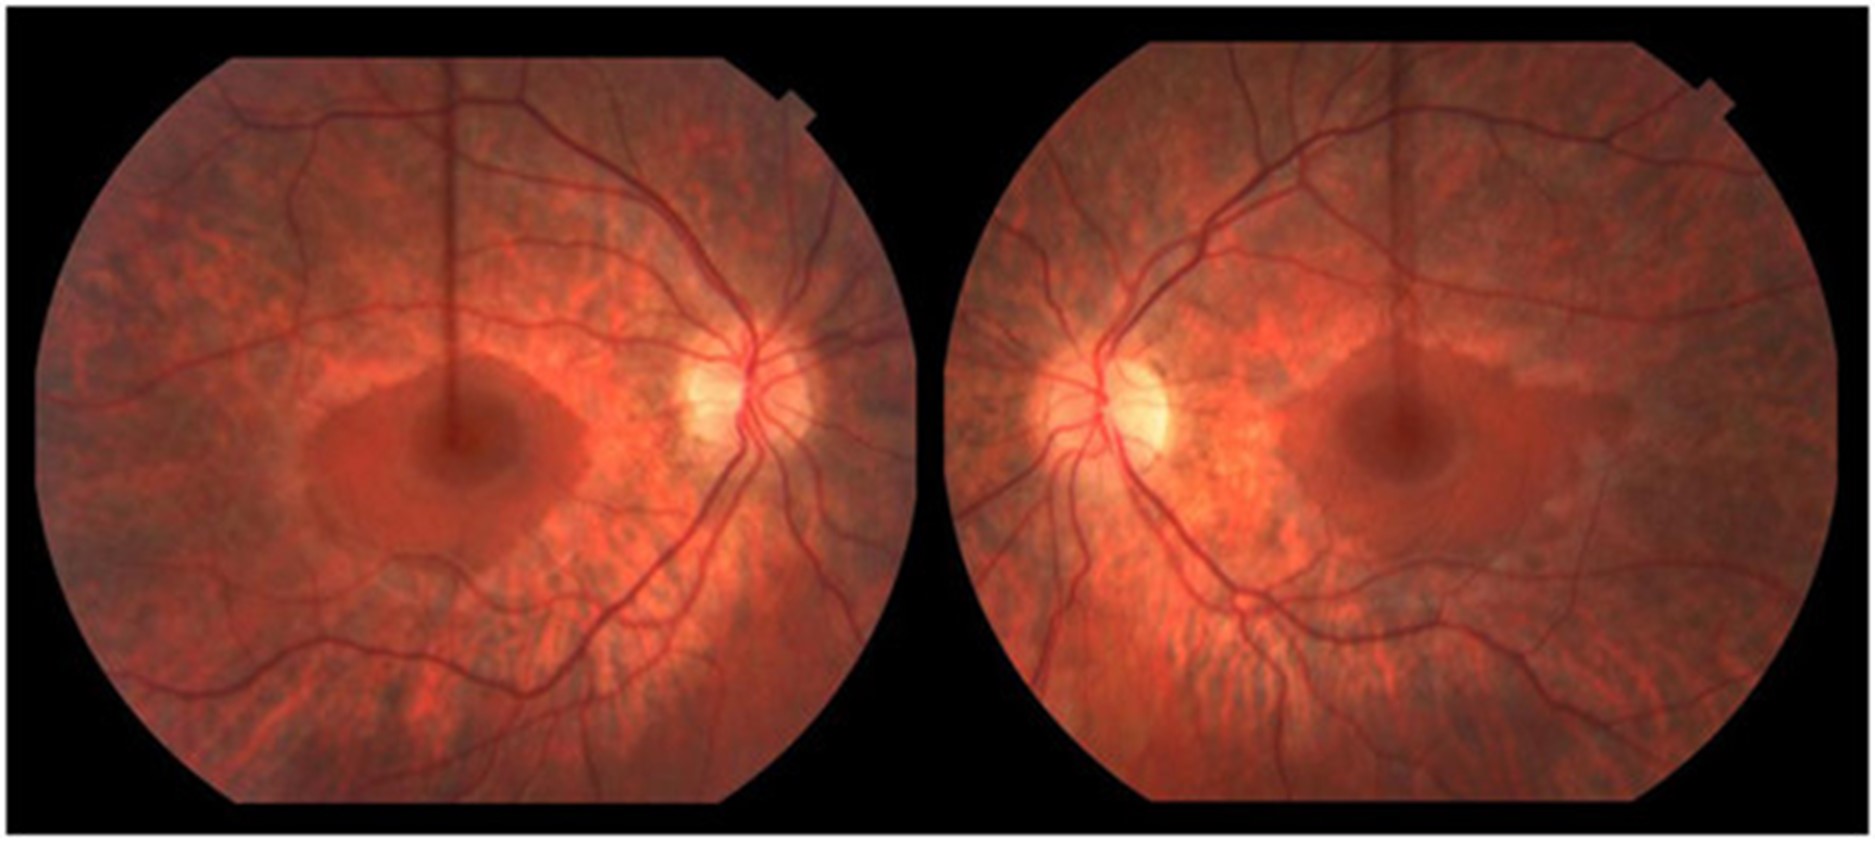

一名 16.5 岁的男孩在 3.5 岁时被诊断出语言表达迟缓和发音困难,这是由中度至重度感音神经性听力障碍引起的。他的语言发展在助听器的帮助下完全正常化。他早期的粗大和精细运动发育正常;他小时候会滑冰和打曲棍球。他在普通课堂环境中的学业成绩很好。11 岁时,他患上了隐匿的进行性步态共济失调。他被发现有双侧高弓足和轻度槌状趾足畸形、弥漫性反射消失和屈肌足底反应。注意到前间室肌肉非常轻度无力,因此使用了踝足矫形器。小纤维感官测试在库存分布中略有下降。振动觉和本体感觉保持完好。有明显的轻度不协调;快速手指运动缓慢,脚跟到胫骨测试受损。Romberg征阴性。神经传导研究(表1) 显示具有脱髓鞘特征的轻度感觉运动性多发性神经病(运动传导速度;20–25 m/sec;正常上肢≥50 m/sec,下肢≥40 m/sec)。感觉和运动神经振幅正常,但腓总神经 CMAP 振幅较低。随着时间的推移,他的高弓足恶化,他的神经传导研究显示进行性脱髓鞘(潜伏期延长增加)和长度依赖性轴突丧失(运动和感觉振幅进行性丧失)的证据。15.5 岁时的眼底镜检查显示广泛的周边视网膜萎缩伴中央黄斑(即严重的视杆细胞功能障碍伴视锥细胞相对保留)与色素性视网膜炎一致(图 1)。视力正常。视觉诱发电位正常。暗视杆状视网膜电图 (ERG) 显示轻度异常,表明周边视网膜的杆状细胞功能障碍。明视锥和 30 Hz 闪烁也异常,表明视锥功能障碍。在他 16.5 岁时的最后一次临床随访中,他在家中可以进行短距离走动,但由于他严重的共济失调,长距离走动需要轮椅。他没有表现出生长或青春期延迟的迹象。他的身高在 10-25百分位之间,并且在 16 岁时,他被注意到具有与年龄相适应的青春期发育;Tanner IV 阴毛和 12-15 mL 睾丸体积。他的认知、语言和视觉都完好无损。他没有肾脏或肝脏受累的临床或生化证据。

这位 14 岁的弟弟在 2 岁时被确诊患有中度至重度感音神经性听力损失,需要助听器。他的早期神经发育正常。他仍然很活跃;最后随访能够滑冰 3 公里和越野滑雪 1-1.5 小时。他不需要踝足矫形器或任何其他辅助设备。他的检查对非常轻度的高弓足和反射减退(二头肌 1+、肱桡肌 1+、三头肌 2+、髌骨 1+、踝反射 0)、屈肌底反应和轻度前间室无力(胫骨前肌 4+/5、腓骨肌)具有重要意义长肌 4+,拇长伸肌 4)。除了脚趾针刺感觉过敏外,感官测试正常。注意到轻微的脚踝紧绷。协调是正常的。神经传导研究(表1) 显示具有脱髓鞘特征的轻度感觉运动性多发性神经病。眼底检查显示广泛的周边视网膜萎缩,中央黄斑不受累。视力和 ERG 正常。他的认知完好无损,并且在常规课堂环境中取得了良好的学业成绩。尽管他的身高一直低于第 5个百分点,但他表现出正常的生长速度。在将近 14 岁的时候,他没有显示出阴毛初现的迹象,Tanner I 阴毛和 5 mL 睾丸体积。他的实际年龄为 13 岁 8 个月,骨龄为 11 岁,符合体质性生长和青春期延迟。他没有显示肾脏或肝脏受累的证据。